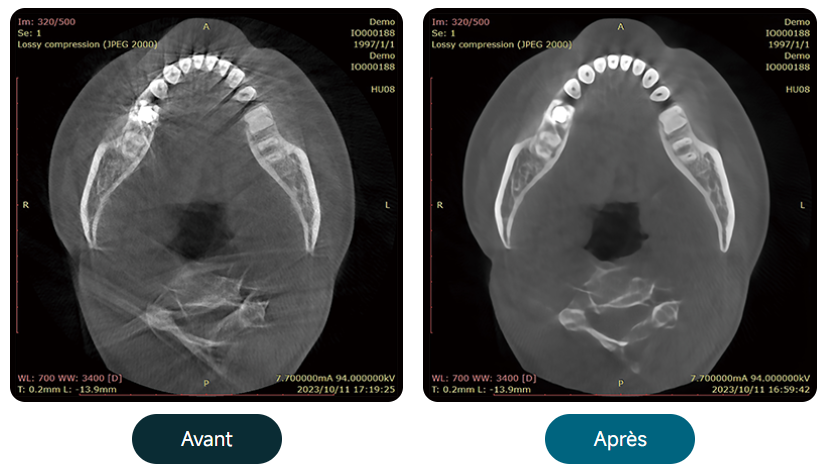

Algorithme de correction des mouvements du patient

Algorithme de réduction des artefacts métalliques

Suppression dynamique du bruit

Dose de rayons X ultra-faible et haute qualité d’image